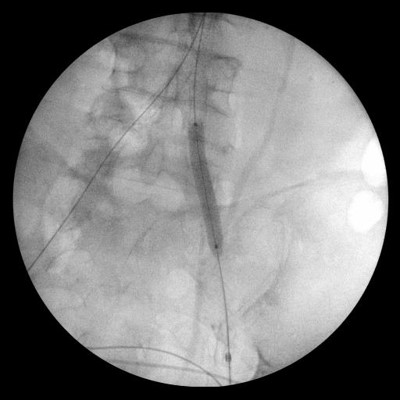

Киссинг  аорты и дополнительное  стентирование подвздошных артерий